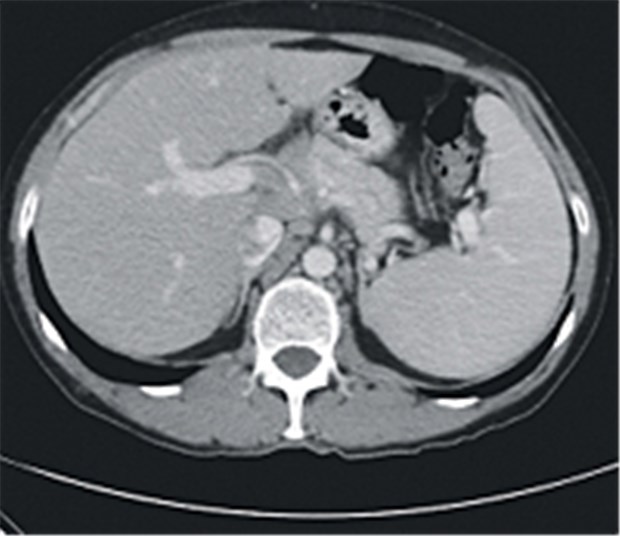

Auf computertomografischen Bildern war bei dem Patienten eine Splenomegalie zu sehen.

Außerdem hatte er subfebrile Temperaturen, Nachtschweiß und leichten Gewichtsverlust. Sonografisch war eine Malignom-verdächtige Induration am unteren Hodenpol nachweisbar. Die Computertomografie ergab unspezifisch vergrößerte thorakale Lymphknoten und eine Splenomegalie (Der Urologe 2011, 50: 71).